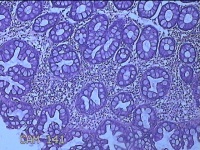

乙状结肠粘膜

性别

男

年龄

52岁

临床诊断

结肠息肉

一般病史

乙状结肠可见息肉

标本名称

大体所见

灰白粉红色组织小米大一团。

自动采图系统很方便,图片采太多没病变的图,几张就够了,而且制片技术急需改进,

有点增生性息肉的感觉